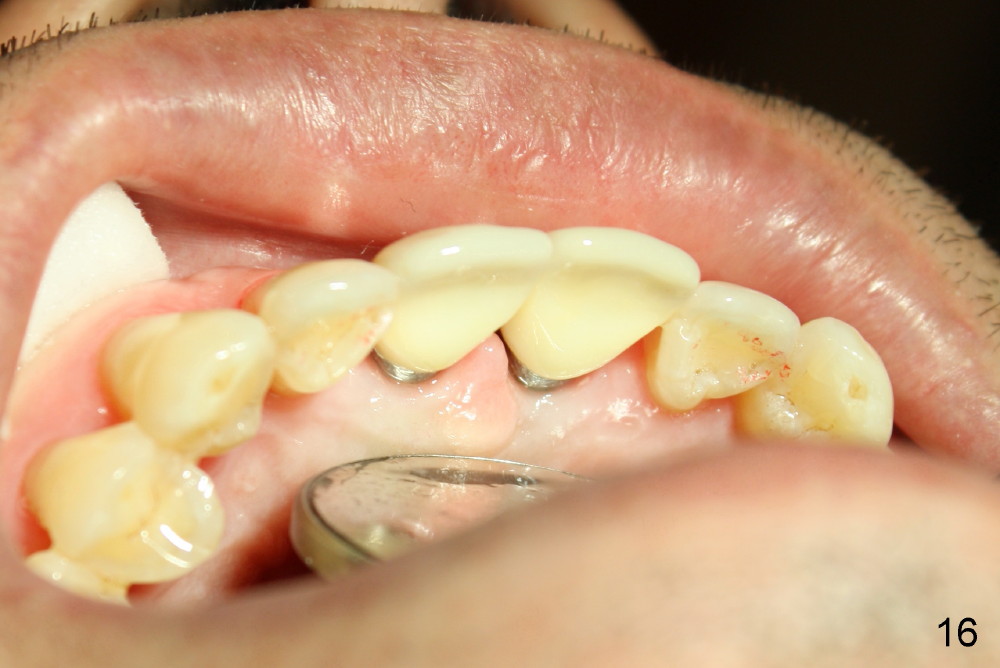

Definitive restoratons (Zirconium crowns) are seated (Fig.15,16). There is no sign of infection. The patient is pleased. In fact the nasal floor does not seem to have been lifted by the implants, as revealed by CT taken 5 years post cementation (Fig.17,18).